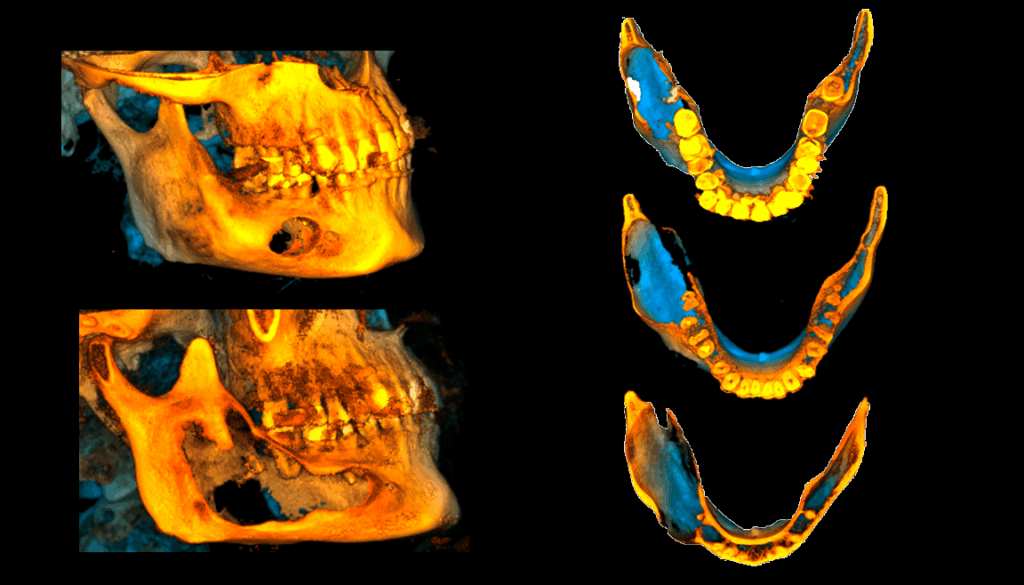

En la reconstrucción 3D se representa la expansión y el adelgazamiento de las corticales de la lesión (Figura 7)

RECONSTRUCCIÓN 3D